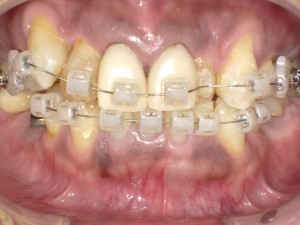

4.治療の開始(装置の装着)

治療のために必要な処置をします。

矯正装置を装着し、歯を動かしていきます。

ブラケットと呼ばれる固定式装置を歯の表面に付けてワイヤーを通し、その力で歯を動かす方式です。ブラケットには、金属のものと白いセラミックのものがあり、セラミックのほうが目立ちません。